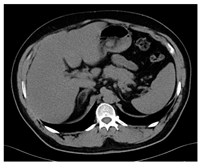

| CT-scan | ![]() | ![]() | ![]() |